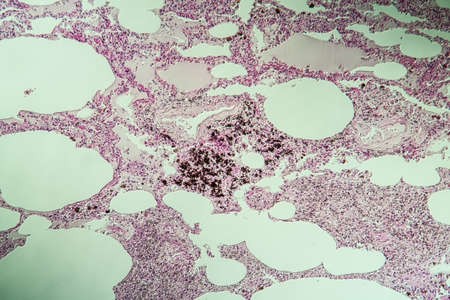

Lung tissue as dust lung under the microscope 100x